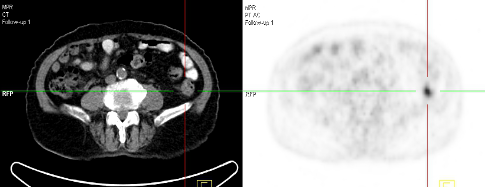

PETCT在疾病的診斷發(fā)面具有如下特點(diǎn):(1)PET-CT能早期診斷腫瘤等疾病。由于腫瘤細(xì)胞代謝活躍,攝取顯像劑能力為正常細(xì)胞的2~10倍,形成圖像上明顯的“高代謝區(qū)”,因此在腫瘤早期尚未產(chǎn)生解剖結(jié)構(gòu)變化前,即能發(fā)現(xiàn)隱匿的微小病灶(大于5mm)。(2)檢查所采用的核素大多數(shù)是構(gòu)成人體生命的基本元素或極為相似的核素,半衰期很短,所接受的劑量相當(dāng)于一次胸部CT掃描的劑量,安全高效,短時(shí)間可以重復(fù)檢查。(3)通過定性和定量分析,能提供有價(jià)值的功能和代謝方面的信息,同時(shí)提供精確的解剖信息,能幫助確定和查找腫瘤的精確位置,其檢查結(jié)果比單獨(dú)的PET或CT有更高的準(zhǔn)確性,特別是顯著提高了對(duì)小病灶的診斷能力。(4)常規(guī)的影像學(xué)檢查是對(duì)選定的身體某些部位進(jìn)行掃描,而PET-CT一次全身掃描(頸、胸、腹、盆腔)僅需近20分鐘左右,能分別獲得PET、CT及兩者融合的全身橫斷面、矢狀面和冠狀面圖像,可直觀的看到疾病在全身的受累部位及情況。(5)可早期發(fā)現(xiàn)腫瘤,確定性質(zhì),其治療費(fèi)用較晚發(fā)現(xiàn)明顯減少,患者生存時(shí)間亦有顯著提高;一次檢查就可準(zhǔn)確判斷大多數(shù)腫瘤的良惡性、是否有轉(zhuǎn)移,轉(zhuǎn)移程度,避免了多種檢查延誤疾病診斷或者制定錯(cuò)誤的治療方案;可準(zhǔn)確對(duì)腫瘤進(jìn)行分期,評(píng)價(jià)治療效果,減少不必要的治療方法和劑量;能準(zhǔn)確判定腫瘤治療后的腫瘤復(fù)發(fā),雖單一檢查費(fèi)用略高,但實(shí)際上避免了不必要的手術(shù)、放化療和住院,總體性價(jià)比突出。